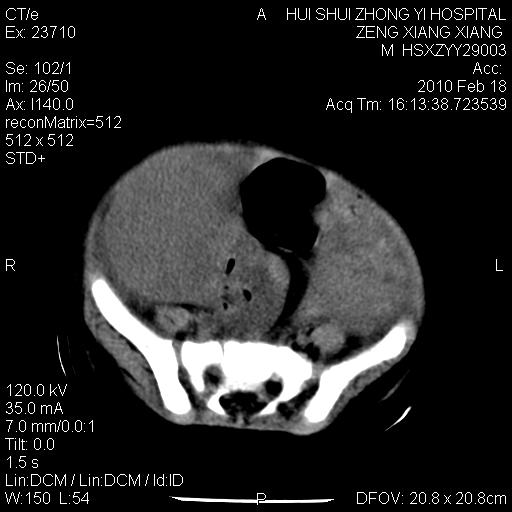

标题: PED3106:男,2岁,腹胀1月。 [打印本页]

标题: PED3106:男,2岁,腹胀1月。

定位腹膜后,肾上腺来源;

定性:恶性神经源性,肾上腺神经节母细胞瘤可能性大。

鉴别:肝母、肾母、肝脏中胚层错构瘤。

依据:年龄、有钙化,肾脏及肝脏受压移位。

肝母细胞瘤可能性大,右肾形态大体可见,不支持肾母细胞瘤,右肾移位不明显,肾上腺神经母细胞瘤可能性不大。